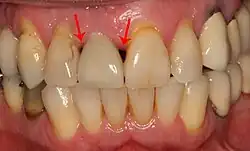

Bone loss (peri-implantitis) on implants over 7 years in a heavy smoker

Fixture show

Recession of the gingiva leads to exposure of the metal abutment under a dental crown.

Black triangles

Black triangles caused by bone loss between implants and natural teeth